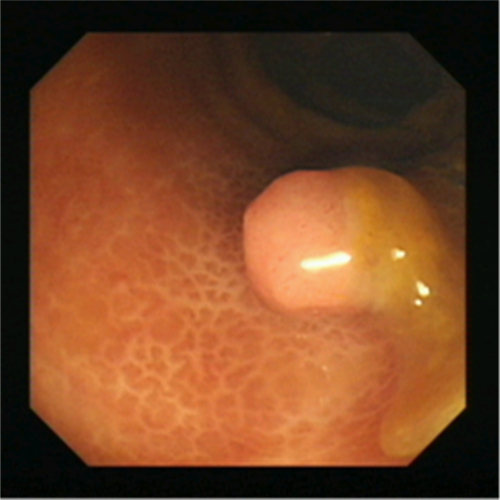

直腸息肉無蒂

直腸息肉良性